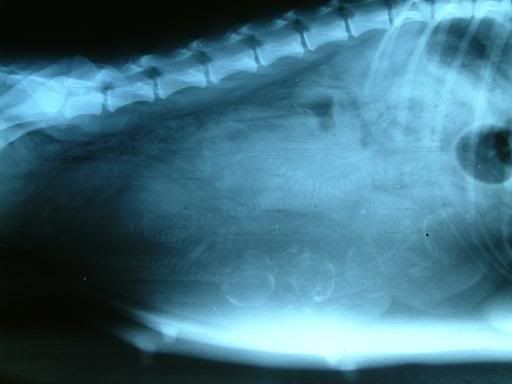

Rontgenfoto drachtige hond

Heeft iemand toevallig een rontgenopname van een drachtige hond? Een foto waar enkele pups (skeletjes) duidelijk op te zien zijn.

En waarvan ik de foto ook mag gebruiken voor een werk voor school

wat mooi te zien al die skeletjes, is dit een foto van jouw hond?